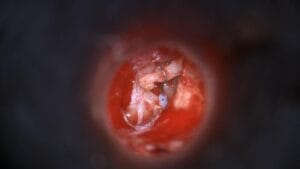

Gastrostomía percutánea guiada por imagen

La Dra. Sikia Wong realiza una gastrostomía percutánea guiada por imagen, mostrando la punción gástrica, colocación de anclajes y sonda.